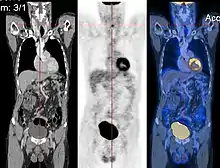

CT image (left), PET image (center) and overlay of both (right) after correct registration.

Image registration is a process that searches for the correct alignment of images.[21][22][23][24] In the simplest case, two images are aligned. Typically, one image is treated as the target image and the other is treated as a source image; the source image is transformed to match the target image. The optimization procedure updates the transformation of the source image based on a similarity value that evaluates the current quality of the alignment. This iterative procedure is repeated until a (local) optimum is found. An example is the registration of CT and PET images to combine structural and metabolic information (see figure).